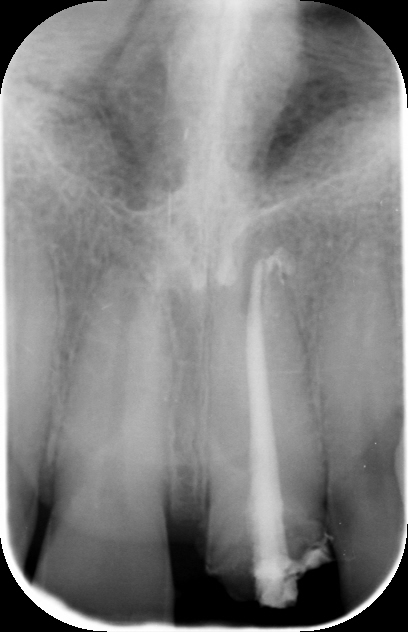

Nuovo perno moncone: Il perno moncone esistente è stato rimosso e sostituito con uno nuovo, realizzato in fibra di vetro, un materiale che offre una maggiore adesione e resistenza nel tempo, oltre a migliorare l'integrazione con la struttura dentale residua.

2. Sostituzione del perno moncone:

Una volta completato il trattamento canalare, è stato posizionato un nuovo perno in fibra di vetro. Questo materiale è stato scelto per la sua elasticità simile a quella della dentina, che riduce il rischio di fratture radicolari rispetto ai perni metallici tradizionali. Inoltre, la fibra di vetro è radiotrasparente, permettendo un migliore monitoraggio radiografico.